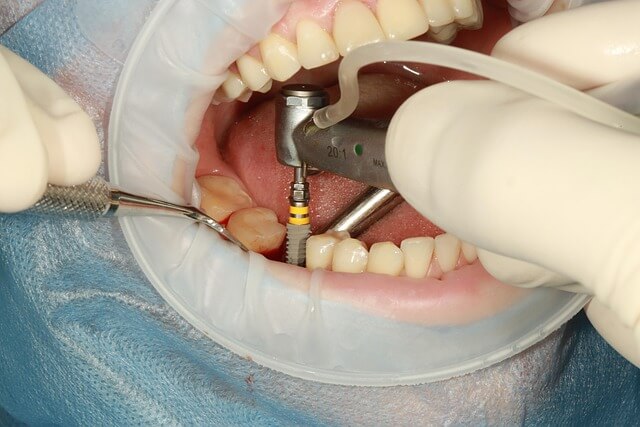

인레이 치료는 생각보다 간단하지만, 2회 내원이 필요했습니다. 처음 방문 때는 충치 부위를 제거하고 본을 떴어요. 이때 치아 모양을 3D 스캐너로 촬영해서 맞춤형 인레이가 제작됩니다. 일주일 뒤 두 번째 내원에서 실제 인레이를 부착했는데, 붙일 때 통증은 전혀 없었어요. 접착 후 검진까지 30분도 안 걸렸습니다.

시술 후 처음 며칠은 약간 어색했지만 바로 적응됐습니다. 특히 식후 양치 시 불편함이 없어서 관리가 훨씬 수월했어요. 인레이는 치아 크라운처럼 완전히 덮지 않기 때문에, 제 치아가 남아 있다는 안정감도 느낄 수 있었습니다.